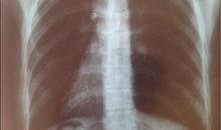

最近在网上看到一个话题,真是让人好奇心爆棚!那就是2023年的最新胸片爆料。你知道嘛,这可不是普通的爆料,而是关于我们身体健康的...